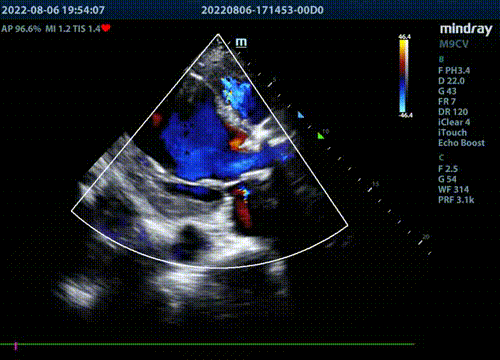

术前超声显示主动脉瓣周大量反流。